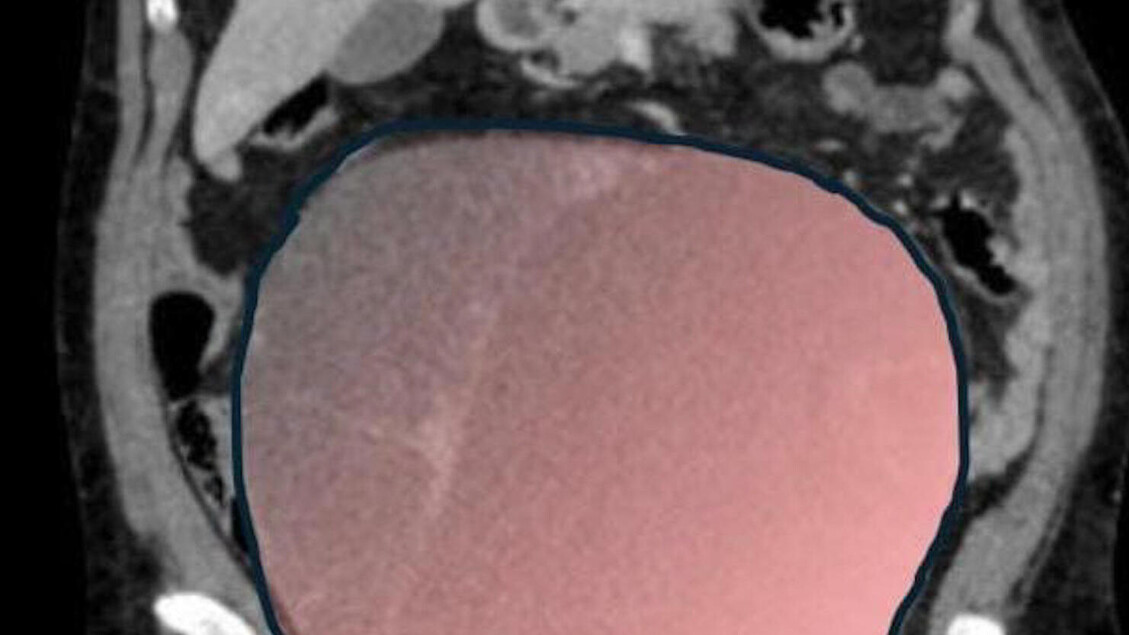

Una donna di 69 anni è stata sottoposta a un intervento chirurgico complesso, durato circa sei ore, presso l’ospedale Sant’Anna di Torino. Il 23 dicembre 2025, la paziente è stata operata per la rimozione di un tumore ovarico di ben 6 chilogrammi, con un diametro di 28 centimetri, il cui volume era paragonabile a quello di una gravidanza gemellare a termine.

La responsabilità della cura di Daniela era stata assunta dalla Chirurgia ginecologica mininvasiva dell’ospedale Sant’Anna, sotto la direzione del dottor Paolo Petruzzelli, che ha definito il caso come un evento “normalmente eccezionale”. La Radiologia ha fornito immagini preoperatorie fondamentali per la pianificazione dell’intervento. Sono stati attivati i servizi della Città della salute e della scienza di Torino, inclusi il Centro accoglienza e servizi e il Gruppo interdisciplinare di cura, per definire il percorso terapeutico più adatto. Un ruolo centrale è stato svolto dall’équipe di Anestesia e Rianimazione, guidata da Mariella Maio. È stata coinvolta anche Anna Opramolla, della Gastroenterologia ed endoscopia digestiva dell’ospedale Regina Margherita, senza preavviso.